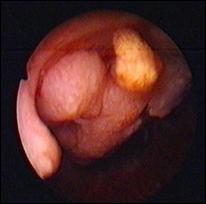

c). Neoplasm de prostata care sangereaza

Figura 66. Pacient cu neoplasm de prostata, anurie si hematurie.